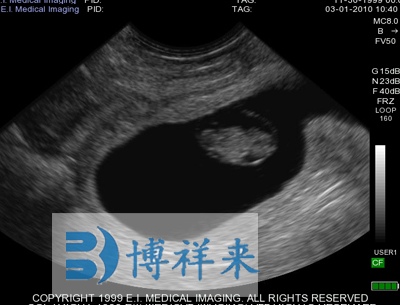

使用对象:牛、马等动物

| 超声类型 | 数字超声 | 产科软件 | 各种动物妊娠期参数表格 |